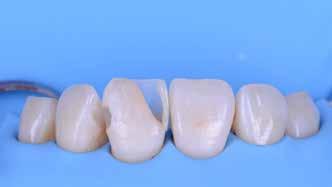

A platinafólia technikát 1896 óta alkalmazzák. Napjainkra az eredeti eljárás már kismértékben módosításra került, de lényegében ugyanazzal a módszerrel történik a platinafóliára készülő koronák és héjak elkészítése. A minimál invazív fogászat egyre szélesebb körben történő elterjedésének köszönhetően ez az eljárás a reneszánszát éli. A pácienseink egyre gyakrabban szeretnék a fogaik alaki, színi vagy helyzeti rendellenességeit a lehető legkisebb saját foganyagveszteség árán korrigáltatni. Az eljárás során 0,025 mm vastag 99,9%-os tisztaságú platinafólia kerül alkalmazásra. Amennyiben a megfelelő technikai háttér és a beavatkozások elvégzéséhez szükséges elméleti és gyakorlati szaktudás is rendelkezésünkre áll, akkor semmi sem állhat az utunkba a pácienseink új mosolyának kialakítása során.

A módszer első lépéseként a gipszből kiöntött csonkokat platinafóliával borítjuk (5. ábra). Az adaptálását követően a felhelyezett fóliát óvatosan eltávolítjuk, felhevítjük, majd ismét visszahelyezzük a csonkokra. Ezt követően történik meg az első kerámiaréteg felvitele (Waschbrand). Az első égetés során csupán egy nagyon vékony réteg kerámia kerül a fólia felszínére (6. ábra). Amikor az égetést követően ezt

a kezdetleges kerámiavázat visszahelyezzük a csonkokra, a kerámia anyagában vékony repedések alakulnak ki. A végleges restaurátum elkészítéséhez szükséges kerámia „köpeny” ekkor áll készen a további kerámiarétegek felvitelére és kiégetésére (opaker réteg, dentin- és zománcmassza felvitele) (7-10. ábra). A készülő fogpótlás végső formai megjelenése rétegenként kerül kialakításra.

A második égetés során szintén csupán egy nagyon vékony réteg transzlucens opalmassza kerül felhelyezésre. A restaurátum formai megjelenésének és a felszíni textúrák kialakítására csak ezt követően kerül sor. A fényégetés során nem alkalmazunk glazúrmasszát. A készre vitel során elérni kívánt, magas fényű polírt kézi eszközök alkalmazásával alakítjuk ki. A restaurátumok végső kidolgozását követően a platinafóliát egy csipesz segítségével óvatosan eltávolítjuk, majd a kifejezetten vékony héjakat a kontroll mintára helyezzük. Ezt követően a pótlások megfelelő illeszkedésén kívül a funkcionális elmozdulások közben kialakuló érintkezéseket és a kontaktpontokat is ellenőrizzük. Az ilyenkor esetlegesen szükségessé váló korrekciók elvégzésére a Ducera® LFC (Dentsply Sirona) kerámiaanyagot használjuk. A kész munka fogorvosi rendelőbe való szállítása előtt kifejezett jelentőséggel bír az elkészült restaurátumok gondos becsomagolása. Az átadni kívánt fogpótlások sérülésmentes szállíthatóságának biztosítása elengedhetetlen az eddigi munkánk védelme szempontjából.

A héjak átadását követően kialakuló állapot valósághű módon történő bemutatása érdekében próbapasztát alkalmaztunk (Try-In-Paste; Variolink® Esthetik Try-In-Paste, Ivoclar Vivadent) (11. ábra). A próba során ellenőrizzük a héjak színét, formáját és transzparenciáját. A próbapaszta alkalmazásának egyik lényeges pontja, hogy a paszta színe egyezzen meg a végleges beragasztás során alkalmazni kíván ragasztóanyag színével. A héjak végleges rögzítése során mindig adhezív rendszereket használunk.

A cikkünkben bemutatásra kerülő eset ellátása során preparációt nem igénylő héjak készítése mellett döntöttünk. A héjak készre vitele során a platinafólia technikát alkalmaztuk. Annak ellenére, hogy az elkészítésre kerülő héjak rendkívül vékonyak, és ezáltal a végleges rögzítésük előtt jelentős törésveszéllyel állunk szemben, összességében mégis olyan minimál invazív kezelési eljárásnak számítanak, amely segítségével kifogástalan esztétikai eredményeket lehet elérni. A fent leírtak alapján bátran javasoljuk e módszer alkalmazását.